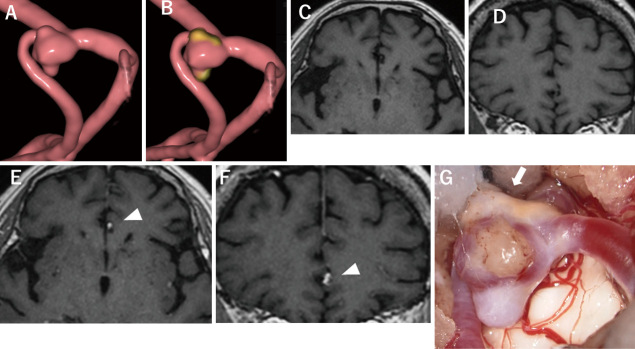

Current magnetic resonance vessel wall imaging enables the detection of atherosclerotic changes in the walls of intracranial aneurysms. Lipid accumulation in the intracranial aneurysm wall is involved in aneurysm neovascularization and chronic inflammation and may lead to aneurysm enlargement and rupture. Therefore, in the present study, we examined the relationship between atherosclerotic changes identified by vessel wall imaging and systemic atherosclerosis-related risk factors. A total of 111 patients with 156 unruptured intracranial aneurysms who underwent magnetic resonance vessel wall imaging and atherosclerotic protein examinations between April 2021 and November 2023 were reviewed. Data on atherosclerotic proteins were obtained from peripheral blood samples. The relationships between aneurysm wall enhancement and patient demographic data, aneurysm morphology, and atherosclerosis-related risk factors were assessed. Fifty-seven of 156 unruptured intracranial aneurysms (36.5%) showed aneurysm wall enhancement. In a univariate logistic regression analysis, age (p = 0.007), male sex (p = 0.023), morphological factors such as maximum diameter (p < 0.001) and irregular shape (p < 0.001), and the levels of apolipoprotein A1 (<0.001) and apolipoprotein B/apolipoprotein A1 (0.004) correlated with aneurysm wall enhancement. In the multivariate logistic regression analysis, age (odds ratio: 1.05, 95% confidence interval: 1.02-1.10), male sex (odds ratio: 3.83, 95% confidence interval: 1.46-10.01), maximum diameter (odds ratio: 1.19, 95% confidence interval: 1.01-1.45), irregular shape (odds ratio: 5.01, 95% confidence interval: 2.10-12.73), and apolipoprotein A1 levels (odds ratio: 0.97, 95% confidence interval: 0.94-0.99) correlated with aneurysm wall enhancement. Low levels of apolipoprotein A1, which may function as an atherosclerotic protein, were associated with specific aneurysm wall features in vessel wall imaging. In future studies, these results will contribute to the identification of factors that promote the destabilization of unruptured intracranial aneurysms.